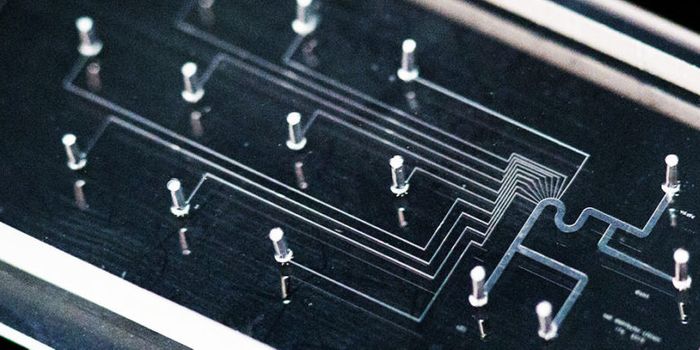

NOV 02, 2016Chemistry & PhysicsDiagnosing Sepsis Earlier to Save Lives Using Microfluidics